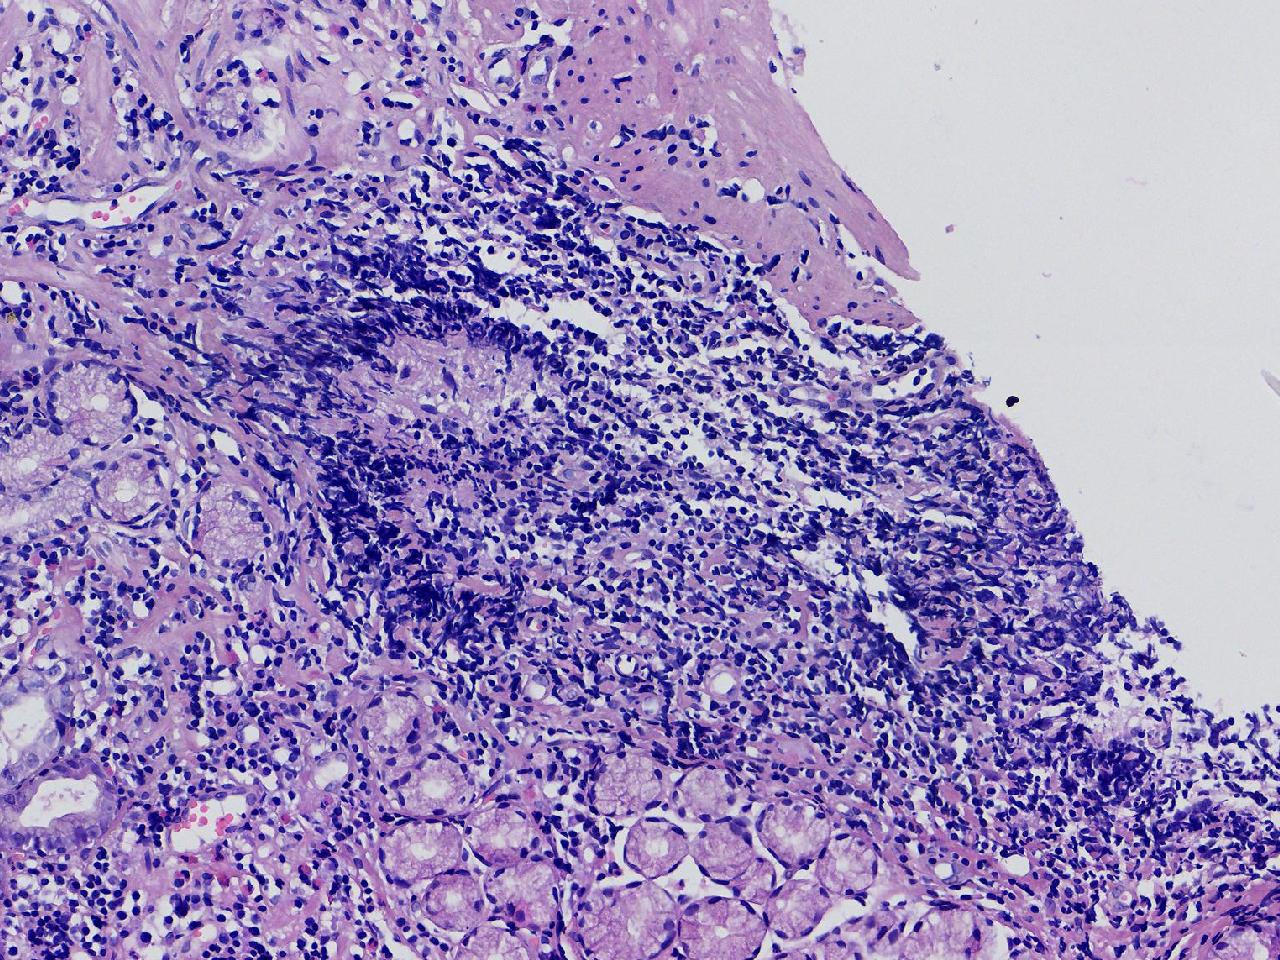

1.间质内淋巴组织有问题吗? 2.有没有低瘤变?

一般病史男,65岁,胃镜活检,胃窦粘膜红白相间,花斑样改变,大弯侧粘膜变薄,血管透见,可见多发片状充血糜烂灶及点状褐色物覆着,活检2块送检,质软弹性可。

标本名称胃窦活检

大体所见灰白色不整形软组织2块,直径均0.2厘米。

慢性萎缩性胃炎伴肠化,固有层淋巴细胞聚集

萎缩性炎,伴有肠化,淋巴组织挤压变形,感觉没有太大的问题。

炎性,无瘤变。